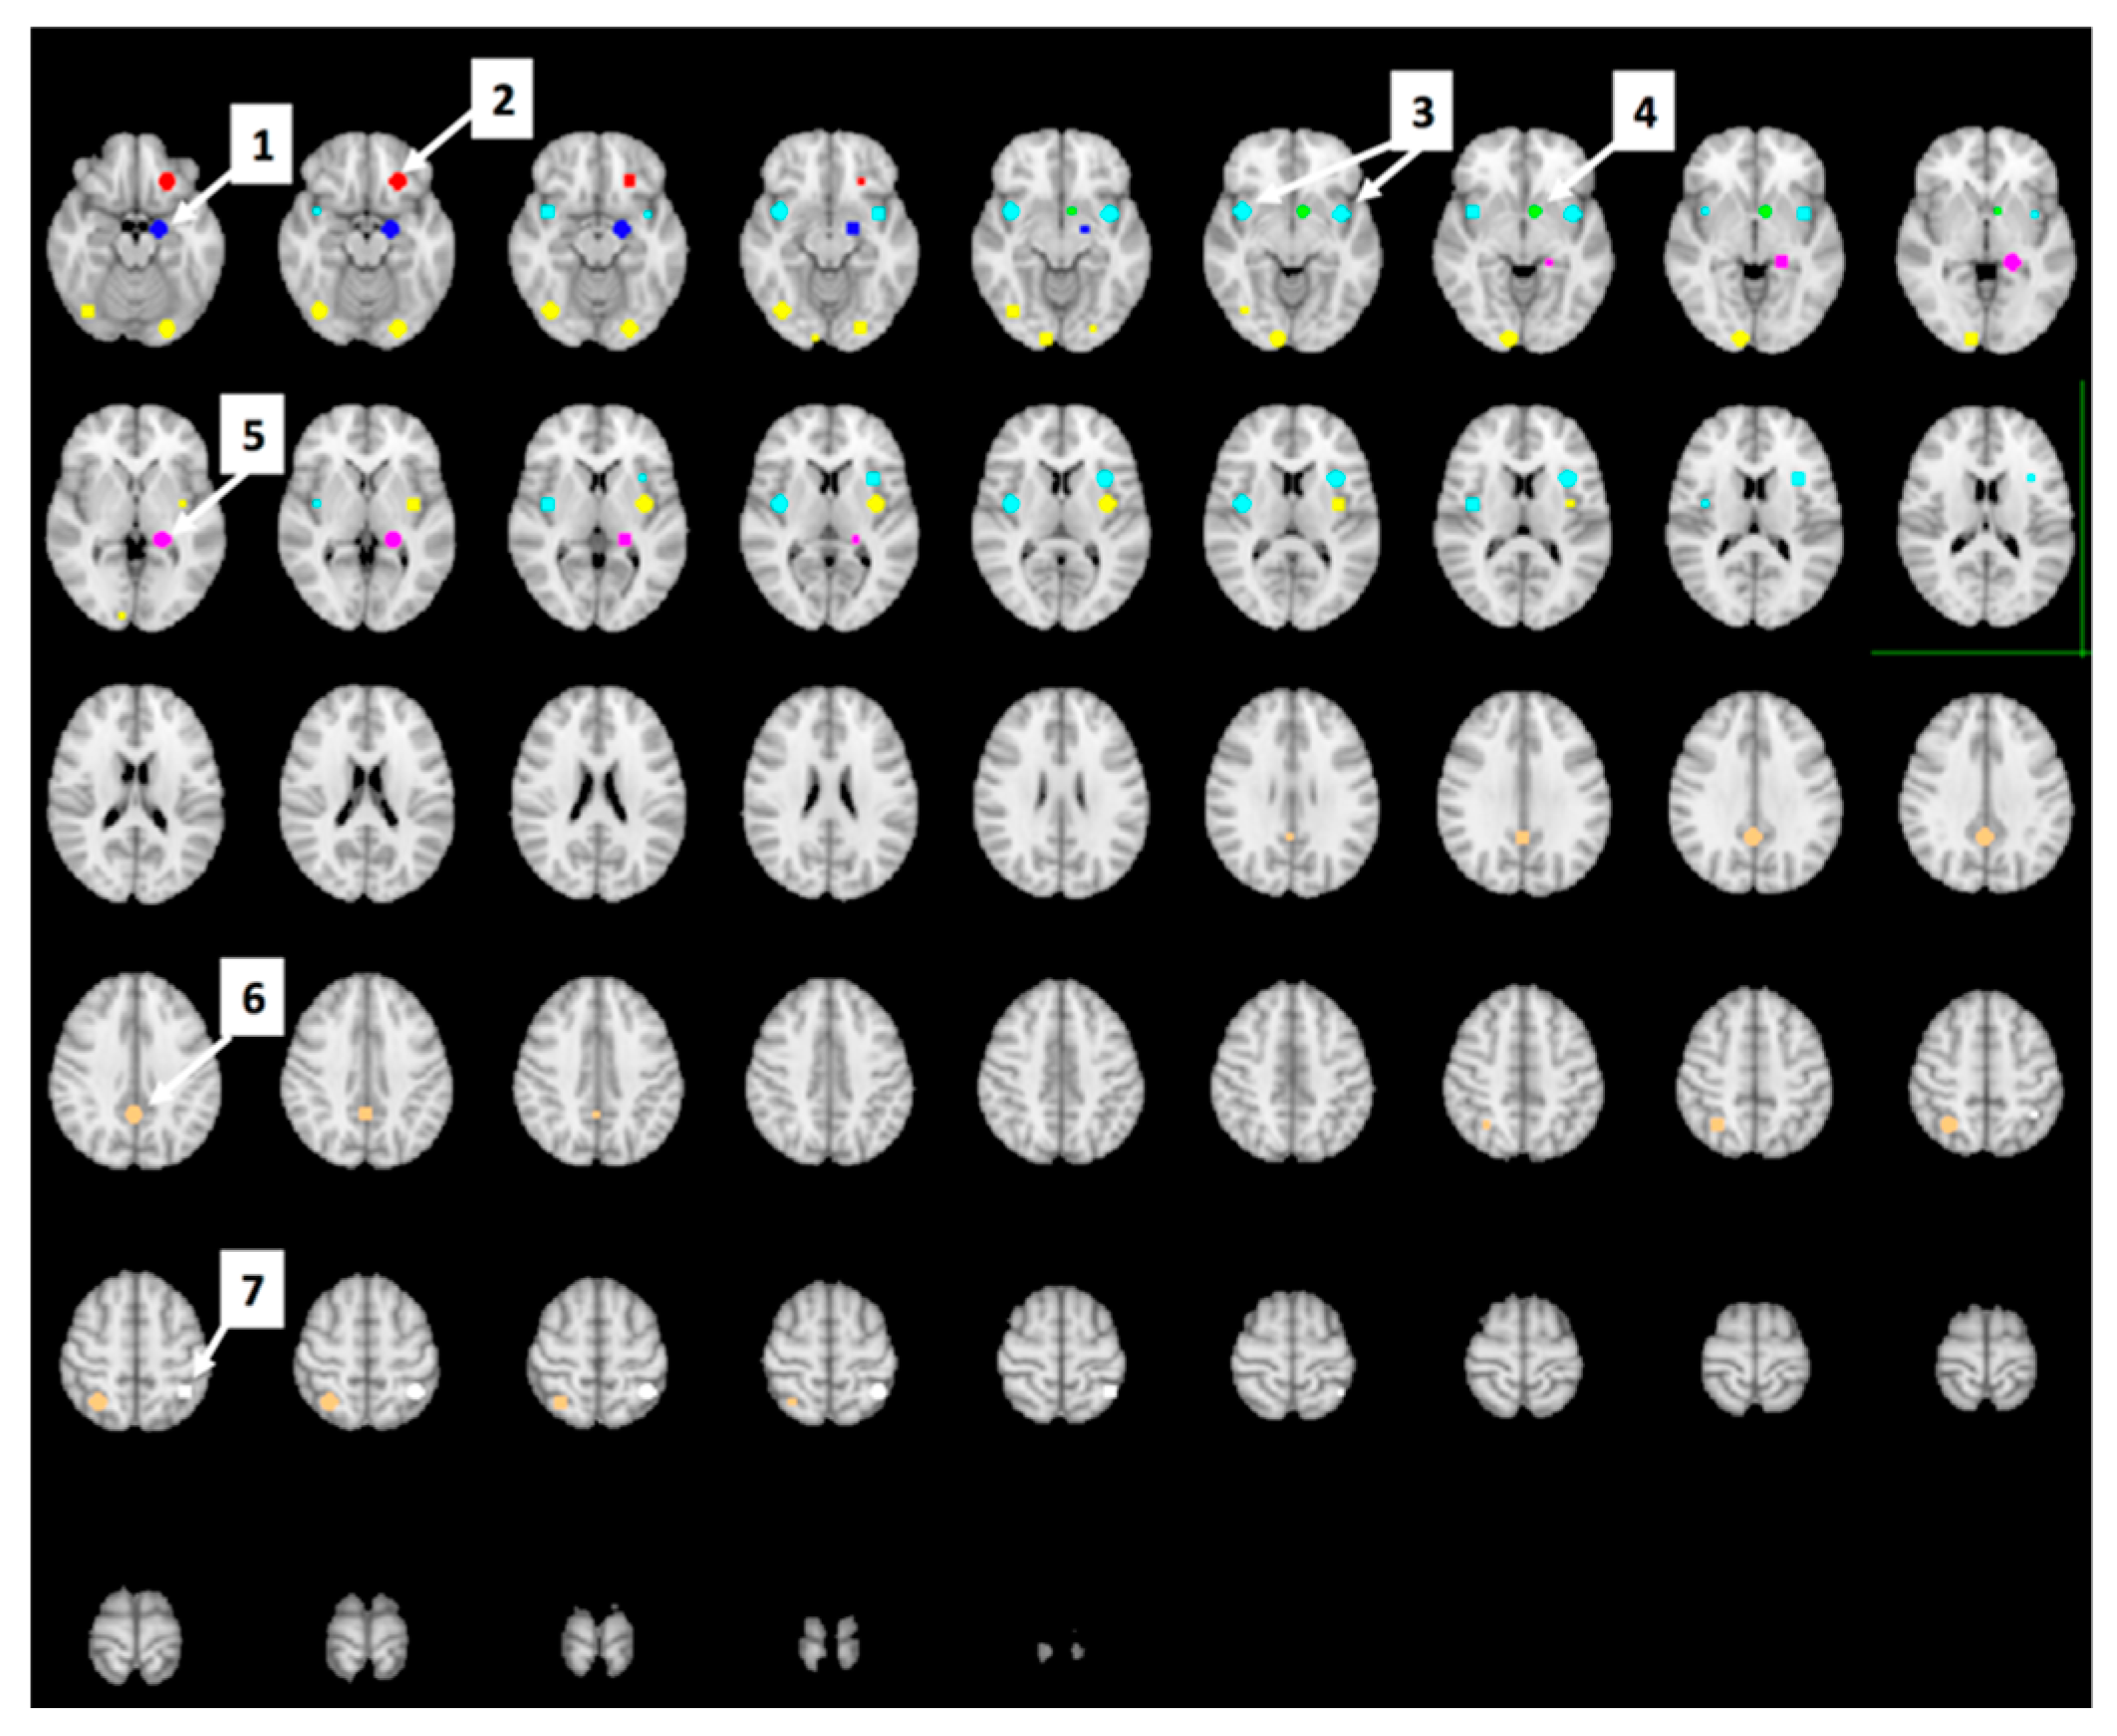

3.5. The Effect of Study Drink on Food-Cue Network ROI Activity during Food Valuation

3.6. Whole Brain Analyses of Activity during Food Valuation Period